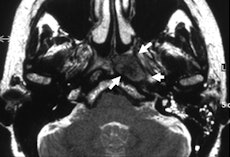

It was possible to evaluate the opening of the eustachian tube during the Valsalva maneuver in all patients. Within the same examination, an underlying problem was identified and its extent delineated in 14 of the 16 patients. In all patients, the anatomical landmarks and structures were clearly depicted and differentiated from pathological abnormalities in the T2-weighted sequence. Involvement of the anatomical structures could be assessed, but the osseous part of auditory tube was depicted with less good image quality than the other parts. In this region, the amount of soft tissue is small and consists only of the mucous membrane, connective tissue, and the periosteum.

"Owing to its high soft-tissue contrast resolution, MRI represents an excellent method to assess anatomical landmarks and abnormalities in and around the auditory tube. Also, information of eustachian tubes opening and closing, its functional state, is clearly visible with the aid of appropriate protocols while the patients perform a Valsalva maneuver," they stated. "To date, functional studies of the eustachian tube have only been performed in normal subjects, but not in patients with clinical symptoms of nonopening of the eustachian tube and abnormal tympanometry."

The eustachian tube, a connection between the middle ear and nasopharynx, is of great importance in normal ventilation for efficient drainage of the middle ear and hearing. Dysfunction causes symptoms such as hearing disturbances and the feeling of fullness of the ear, and these clinical symptoms can indicate serious diseases such as chronic inflammation of the middle ear or the mastoid, cholesteatoma, or malignant processes affecting nasopharyngeal, inner, or middle ear regions, the authors wrote.